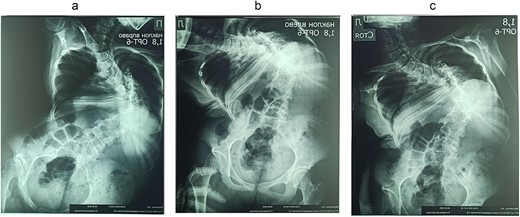

On the preoperative anterior–posterior X-ray, the Cobb angle was 110°; violation of frontal balance—13 cm (Fig. 2).

The rigidity of the scoliotic arch is noted on functional X-rays and on stretching (Fig. 3).

Preoperative functional X-ray: (a) inclination to the right, (b) inclination to the left, and (c) on stretching.